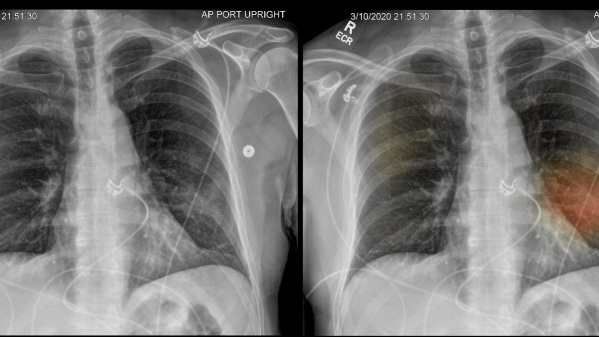

Para el estudio, el equipo de investigadores siguió a 83 pacientes con COVID-19 después de que fueran dados de alta de un hospital. El seguimiento se realizó con supervisión a los 3, 6 y 12 meses. En cada seguimiento, los participantes se sometieron a una evaluación clínica, que incluía medidas de qué tan bien estaban funcionando sus pulmones, una prueba de caminata y una tomografía computarizada de su tórax. Los resultados demostraron que durante un período de 12 meses, la mayoría de los pacientes mostraron una mejoría en los síntomas, la capacidad de ejercicio y los cambios en la TC relacionados con COVID-19. Sin embargo, algo más del 30% de los participantes todavía mostraban un funcionamiento pulmonar reducido, particularmente la eficiencia con la que sus pulmones transfirieron oxígeno a la sangre.

Además, alrededor del 25% de los participantes mostraron signos de cambios en sus pulmones en las tomografías computarizadas. “En primer lugar, nuestra investigación proporciona evidencia de que se requiere un seguimiento respiratorio de rutina de los pacientes hospitalizados con neumonía por COVID-19 -explicó Yihua Wang, coautor del estudio-. Se requiere investigar si el ejercicio programado ayuda a los sujetos a recuperarse más rápidamente. Finalmente, demostramos que la necesidad de estrategias de tratamiento para prevenir el desarrollo de cambios pulmonares relacionados con COVID-19 a largo plazo”.

El promedio de edad de los participantes fue de 60 años. En la mayoría de ellos se observó una mejoría temporal en la fisiología pulmonar y la capacidad de ejercicio; sin embargo, persistieron anomalías fisiológicas y radiográficas en algunos pacientes con COVID-19 a los 12 meses después del alta.

Detectaron una reducción significativa en la capacidad de difusión pulmonar (DLCO) durante el período de estudio, con promedio del 77% de la predicción a los 3 meses, el 76% a los 6 meses y el 88% a los 12 meses después del alta. A un año del alta, los cambios radiológicos persistieron en e 24% de las personas. Los profesionales concluyeron que se justifica el seguimiento respiratorio de rutina de los pacientes hospitalizados con neumonía COVID-19.